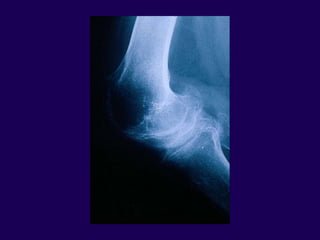

Infection in Total Knee

Arthroplasty

Complications in Arthroplasty

Infection – Risk Factors

l Skin ulcerations / necrosis

l Rheumatoid Arthritis

l Previous hip/knee operation

l Recurrent UTI

l Oral corticosteroids

l Chronic renal insufficiency

l Diabetes

l Neoplasm requiring chemo

l Tooth extraction

Infection – Clinical Course

l Pain #1

l Swelling

l Fever

l Wound breakdown drainage

Windsor et al

JBJS; 1990